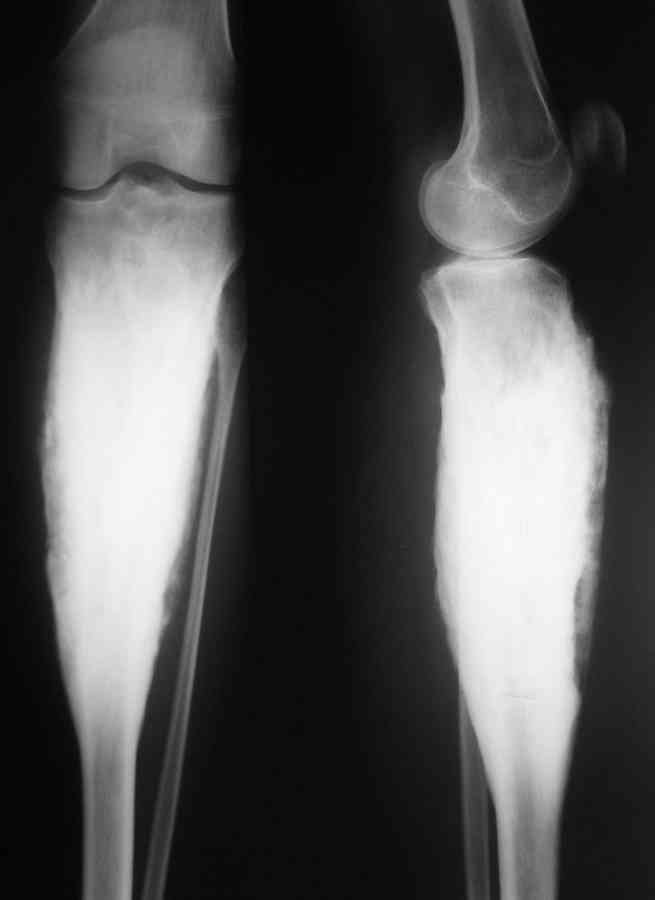

Остеомиелит Гарре

Господа, обратилась девушка 20 с небольшим лет.Больна с 2002 года. остеомиелит Гарре. Подтвержден гистологически.

Чем можно помочь? Кто этим занимается серьезно? И вообще какие подходы в лечении?С уважением Александр Артемьев